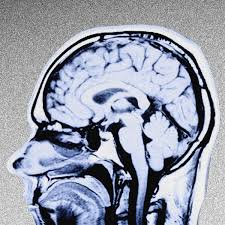

أعراض الحالات أو المرض المزعوم كانت غريبة ومخيفة جدا مثل: مشاكل في السمع والتوازن، جلطات دماغية، مشاكل في النطق، نزيف من الأنف، اصابات دماغية، صمم كليّ، وغيرها من الأعراض

ومن أكثر الأعراض الغريبة هو نسيان الشخص لبعض الرموز والكلمات، وكذلك الصعوبة في قراءة النصوص والتركيز

الأمر مثبت وتمت تجربته على الحيوانات وكانت نتائج مخيفه، تسببت باضرار عالية في ادمغة الفئران و تلف الخلايا والأعصاب

صار واضح ان لترددات المايكرويف علاقة بالقضية لانها اثبتت امكانيتها في التلاعب بالجسم والعقل البشري، وممكن نفسر إن هذا سلاح طاقة.. وذهبت أصابع الإتهام مباشرة إلى روسيا لأنه عدو للولايات المتحدة وغير مستبعد إن عندها الإمكانيات على صناعة أسلحة سرية بهذي الخطورة والتطور